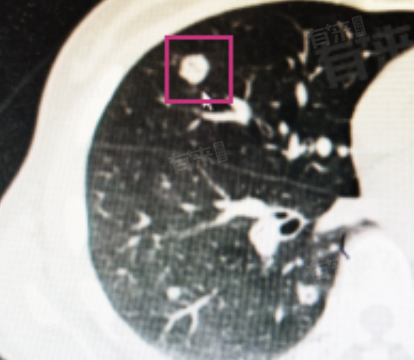

2、恶性可能性相对较高:研究表明,在肺、乳腺等器官中,实性结节恶变几率高于囊性或混合性结节。以肺部为例,实性肺结节若直径较大、形态不规则、有毛刺征等,恶性概率显著上升。这是因为癌细胞大量增殖形成的实体病灶,更易呈现为实性结节,威胁患者生命健康。